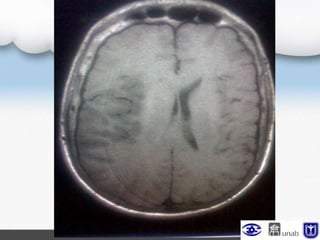

POP Día 15

Neurocirugía

Es llevado a duroplastia,

craneoplastia,

colgajo local vecindad

POP Día 39

POP Craneoplastia